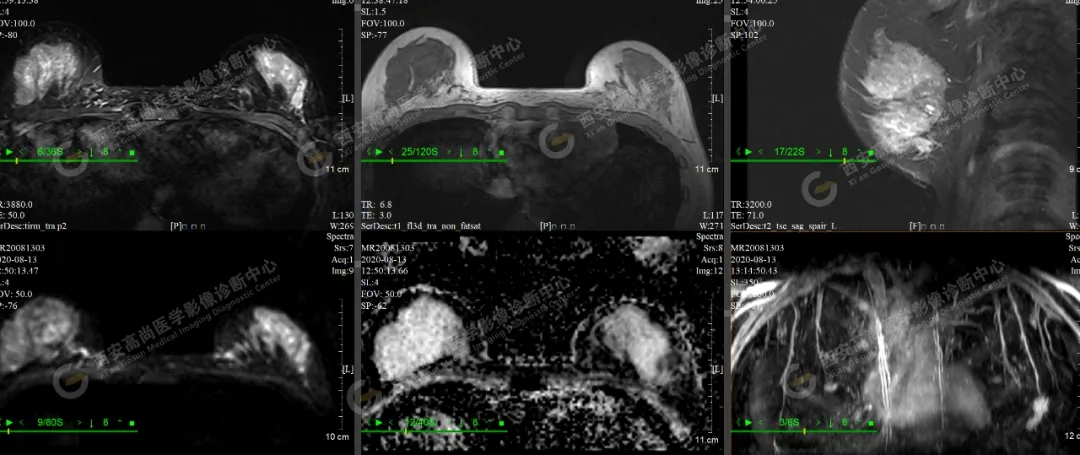

【病例二】女,46歲,左側(cè)乳腺5點(diǎn)方向乳腺Ca(BI-RADS IV-V級(jí)),左側(cè)腋窩多發(fā)腫大淋巴結(jié)轉(zhuǎn)移。